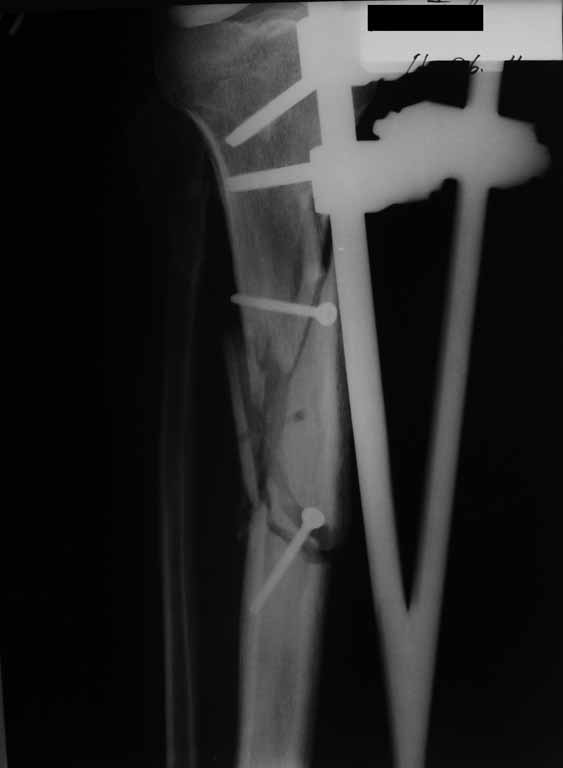

Привожу пример: Пациент с открытой тяжелой ЧМТ.

Диагноз при поступлении: Открытый оскольчатый перелом свода и основания черепа,субдуральная гематома, ушиб головного мозга тяжелой степени. Открытый оскольчатый перелом костей правой голени. Шок 3 Кома 3

При поступлении оперирован : трепанация, ПХО, остеосинтез голени.

Консолидация в аппарате внешней фиксации к 2 месяцам. Аппарат снят через 2,5 месяца.

Фото в приложении.